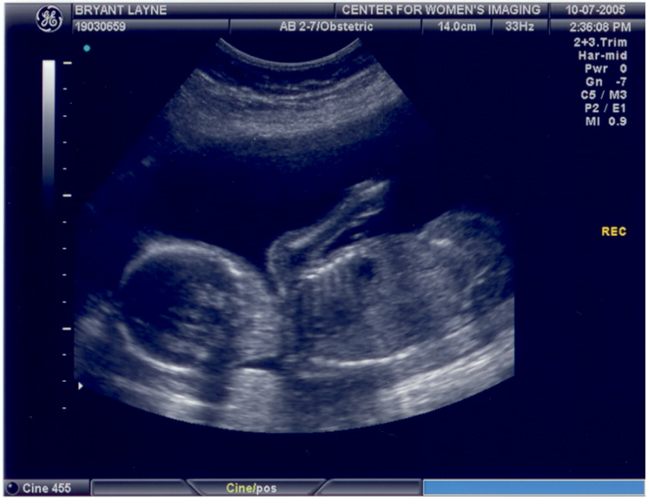

Caroline's Second Ultrasound

These pictures were taken on October 7th at about 20 weeks.